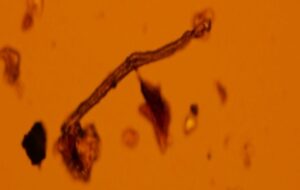

Microplastics Found in Every Human Placenta Tested, Study Finds It’s been over three years since scientists first found microplastics swimming in four